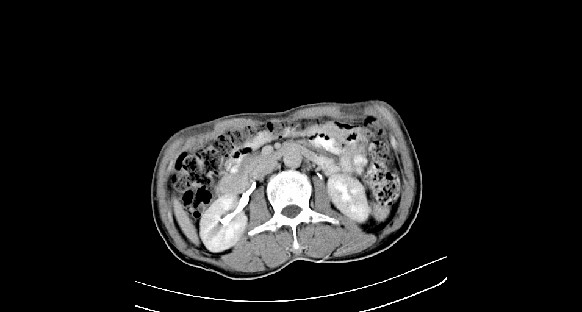

男性,70岁,体检b超发现左肾占位,请各位战友发表一下观点

左肾有两个病灶,且较大的病灶内可见点状钙化灶,增强扫描边缘也是呈渐进性强化,中央部分未见明显强化